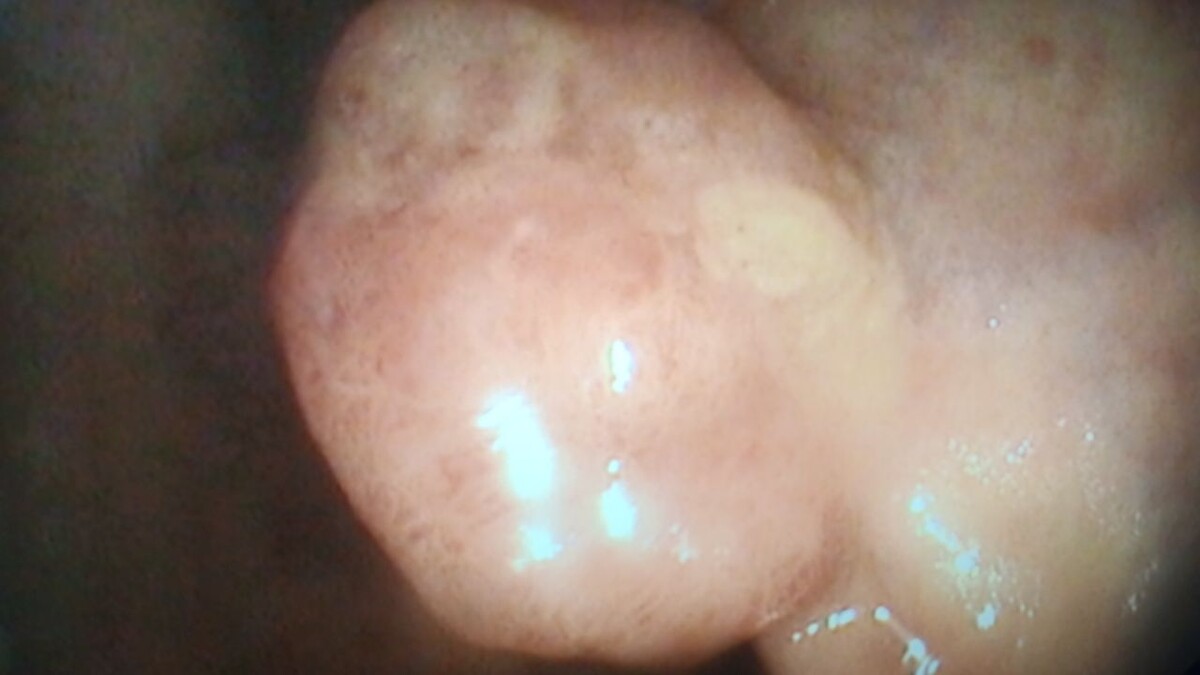

Сегодняшняя находка при плановой колоноскопии. Пациентка 60 лет. Жалоб не было. Полип в средней трети прямой кишки 1,5 см в диаметре. По внешнему виду - тубулярная аденома. Ждём гистологию. Записал на плановое удаление.